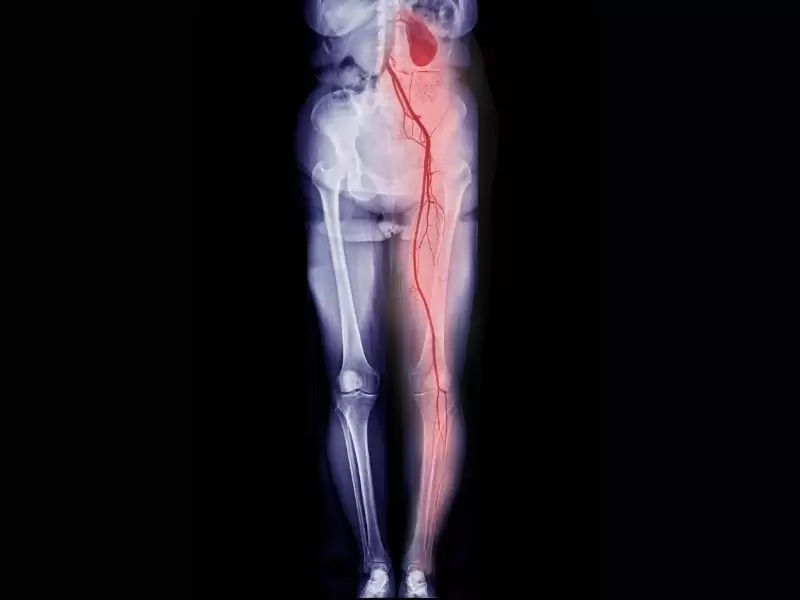

Fotoğraf Galerisi

Hastanemizi daha yakından görün